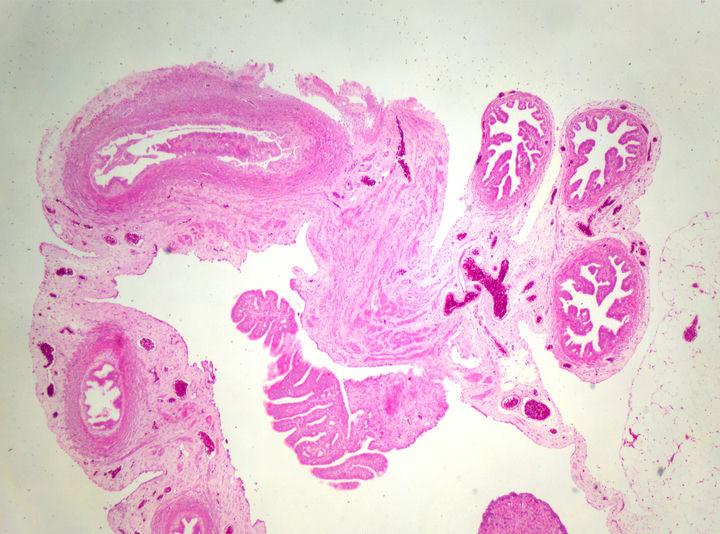

生物显微镜下的卵巢病理切片

病理切片是病理科医生确诊病症的重要工具,观察病理切片一般使用生物显微镜明场观察,一款好的病理切片显微镜,不仅要求使用舒适,还要成像清晰。在生物显微镜ML31的观察下,经过HE染色的卵巢切片呈粉红色,并呈现出丰富而复杂的细节。

卵巢,作为女性生殖系统的重要器官,负责产生卵子和分泌性激素。透过生物显微镜ML31,我们可以看到许多不同种类的细胞。其中较突出的是卵原细胞,这是卵巢中产生卵子的母细胞。在染色切片中,卵原细胞呈现出较大的体积和较深的染色,与其他细胞有所区别。

通过生物显微镜ML31观察卵巢染色切片,我们可以了解卵巢的基本结构和功能。这不仅有助于我们对生殖系统的理解,也为研究卵巢疾病的病因、病理和治疗方法提供了重要依据。